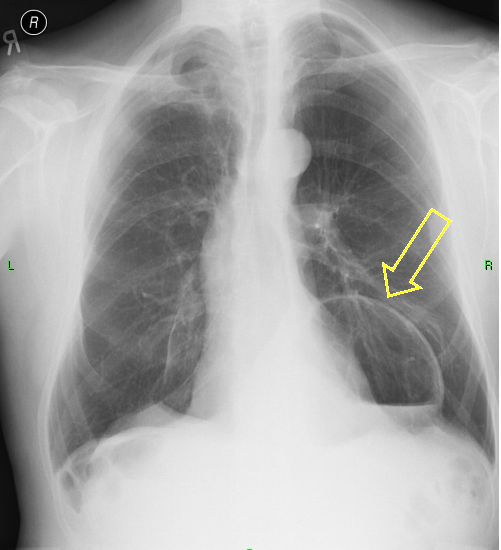

23. Pulmonary metastases, bidirectional (PA and right lateral) plain chest radiograph.

51 year old woman, endometrial carcinoma. Numerous ring shadows bilaterally in basal dominance (max. appr. 12 mm). Left pleural effusion of one finger wide.